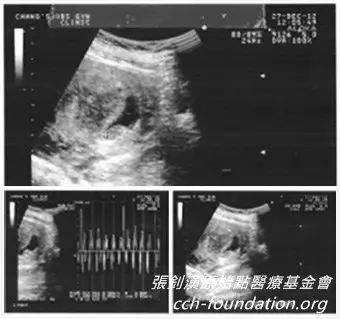

101年12月27日 近第7周产检,还有心跳声

102年 1月23日 近第11周产检,因连续三天不正常出血,血色暗沉,超音波检查发现胎儿没有成形并且萎缩,无生命迹象